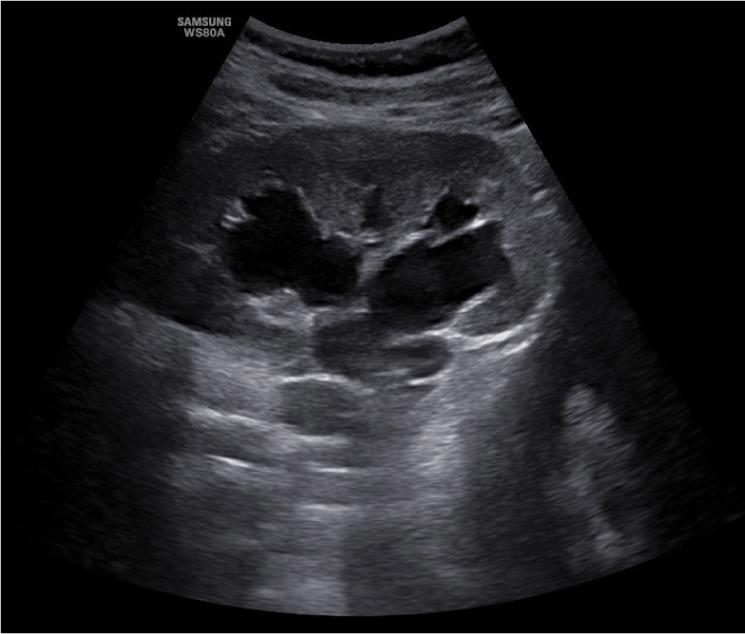

Fig. 2.

Ultrasound assessment of the right kidney (longitudinal section). Visible dilatation of the pelvis and major calyces